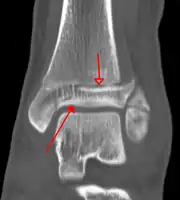

On clinical examination, it is important to evaluate the exact location of the pain, the range of motion and the condition of the nerves[11]. It is important to palpate the calf bone (fibula) because there may be an associated fracture proximally (Maisonneuve fracture)[12], and to palpate the sole of the foot to look for a Jones fracture at the base of fifth metatarsal [13]Evaluation of ankle injuries for fracture is done with the Ottawa ankle rules, a set of rules that were developed to minimize unnecessary X-rays.[14] There are three x-ray views in a complete ankle series: anteroposterior, lateral, and oblique [15]. The mortise view an anteroposterior x-ray taken with the ankle internally rotated until the lateral malleolus is on the same horizontal plane as the medial malleolus, resulting in a position where there normally is no superimposition of tibia and fibula on each other.[16]

On X-rays, there can be a fracture of the medial malleolus, the lateral malleolus, or of the anterior/posterior margin of the distal tibia. [17] If both the lateral and medial malleoli are broken, this is called a bimalleolar fracture[18]. If the posterior malleolus is also fractured, this is called a trimalleolar fracture. [19]